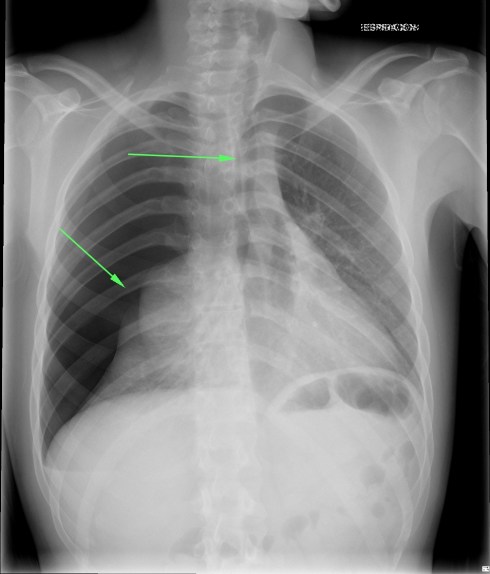

CASO: sospecha de neumonía.

Hallazgos:

- En un principio podríamos decir que existe un aumento de densidad retrocardiaco que podría ser compatible con condensación neumónica a dicho nivel, sin embargo estamos ante una placa poco inspirada, lo cual puede llevarnos a cometer errores diagnósticos.

- Se recomendó volver a realizar la radiografía, observar a continuación:

Ya no se observa el aumento de densidad retrocardiaco, la placa es normal.

INSPIRACIÓN: Una placa bien inspirada es aquella en la que se observar 6-7 arcos costales anteriores o 10-11 arcos costales posteriores. Lo contrario puede producir imágenes falsas de condensaciones o de seudocardiomegalia.